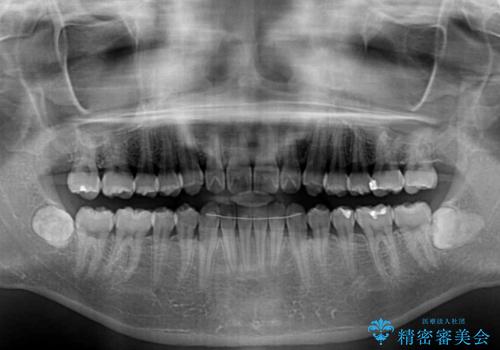

- 下唇に上の前歯が当たることを気にして来院された患者様です。

上顎の親知らずを抜去し、歯列全体を後方に移動させるとともに、IPR(歯と歯の間を削る)を行うことで口元の閉じにくさを改善していくこととしました。

咬合力が強く、マウスピースを介した咬み込みが顕著であったため、奥歯の咬みにくさやIPRのスペースが改善しにくく、治療期間が思った以上にかかってしまいました。